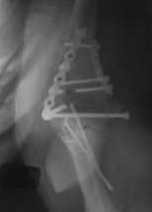

Уважаемые коллеги! Нужен Ваш совет, Подскажите пожалуйста, как можно в дальнейшем этому больному помочь. В марте первая операция, пришлось оперировать на 16 сутки в виду инфицированных садин и анемии. Заживление первичным натяжением,раняя разработка после операции, а через 2 нед болевой синдром,и постепенно движения в локтевом суставе ограничились до полного анкилоза. Повторно через 4 месяца вторая операция" артролиз,удаление оссификатов, удаление фиксаторов, реостеосинтез этой же реконструкционной пластиной и винтом" интраоперационно после удаления оссификатов и фиксаторов обнаружил, что перелом не сросшиеся, поэтому пришлось синтезировать заново. Зажило рана первично, объем движений в локтевом суставе сгибание 70, разгибание160, ротационные движения востановились полностью,вроде бы успокоились. Опять постепенно в течении 8 нед после повторной операции постепенно движения ограничились до 80 - 110, на снимке оссификат. Снимки во вложении, буду рад Вашим советам. Спасибо!С уважением Шухрат.